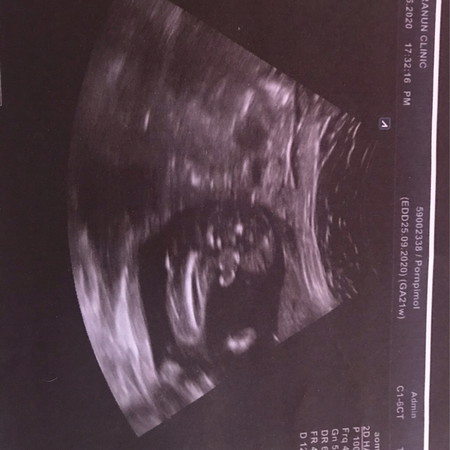

ท้องได้6เดือนแล้วค่ะ

แม่ๆช่วยดูทีว่า ญ หรือ ช ค่ะ

เราว่า ชายนะคะ รอบหน้าถามคุณหมอเลยค่า

หมอว่าไงบ้างค่ะ เราเดาว่าชายค่ะ

โด่ออกมาแบบนี้น่าจะชายนะคะ

ชายจ้า จู๋โผล่ขนาดนั้น

ชายค่ะ มีจู๋โผล่ออกมา